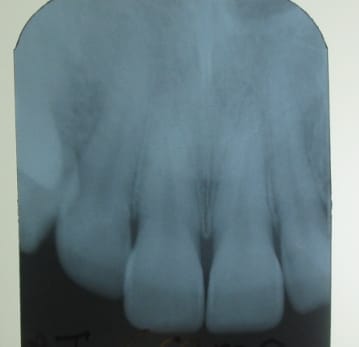

J'oubliais : la radio prouve que l'état parodontal est habituellement sain.

Rétroalvéolaire 19 mars 08 kyskgi - Eugenol